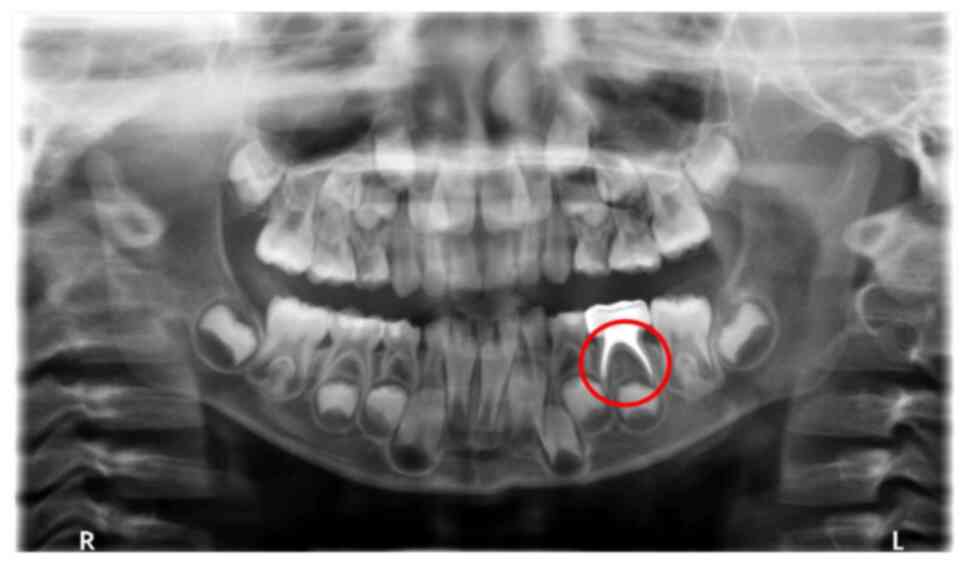

The efficacy of the treatments were evaluated 6 months after surgery. X-rays from Group B were used as examples for efficacy evaluation. No abnormal images were detected of the root and germ of the permanent tooth of the left lower second deciduous molar, which indicated effective treatment 6 months following surgical treatment (Fig. 3). Conversely, the distal root resorption of the right lower primary molar displayed a low periapical density shadow, thus was recorded as an ineffective treatment (Fig. 4). The observation of treatment outcomes at 6 and 12 months post-treatment reinforced the distinctions demonstrated between the various treatments applied in the present study. Imaging of the effectively treated teeth exhibited normalcy in the periapical region, whereas ineffectively treated teeth demonstrated significant abnormal shadows. These results highlighted the role of research in assessing therapeutic effects in clinical applications and may offer practical insights for the long-term management of periapical inflammation of deciduous teeth.

Figure 4

Abnormal images taken from group B, showing distal root resorption (encircled root) of the right lower first primary molar with low periapical density shadow.